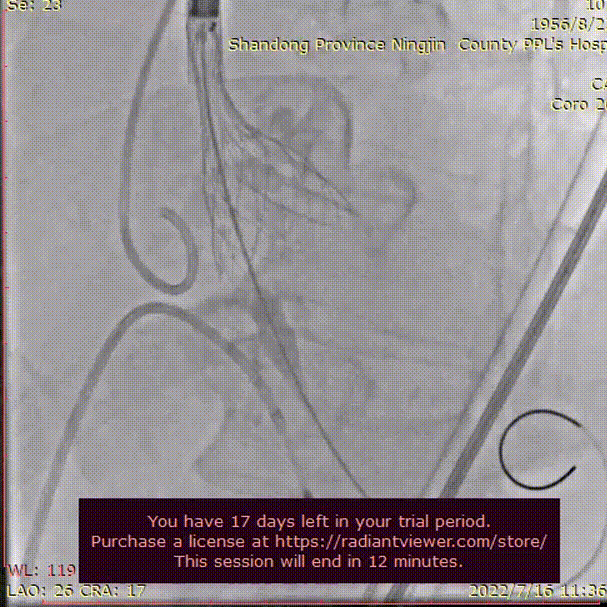

手术过程概览

行冠脉造影,LM末端50%狭窄,PDA近中段50-60%狭窄,中段90%狭窄,LCX近中段60-70%狭窄,RCA全程50-70%狭窄,PDA近中段50-60%狭窄,前向血流均为TIMI3级。

左冠脉造影

右冠脉造影

使用3.0*23mm支架处理病变位置,支架植入后造影显示血管灌注良好。

LAD冠脉支架植入

支架植入后评估

行主动脉根部造影,猪尾确定选择最佳释放体位,观察瓣叶活动,选择合适体位跨瓣。

主动脉根部根部造影

球囊预扩

术者团队用22mm球囊预扩,结合瓣环及球囊预扩情况,预装AV26型号瓣膜。

输送器过弓

初始定位

术者结合DSA影像,多角度观察瓣膜情况,瓣膜释放至工作位造影评估并最终释放。

释放至工作位

完全释放

无明显返流,瓣膜形态佳,工作稳定。手术顺利结束。